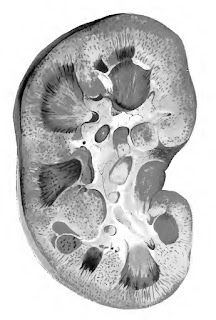

It was a disease predominantly of the young, and the clinical course of most, particularly children, followed the typical pattern of post-Streptococcal disease: The symptom which commonly first attracts notice is oedema … the urine is darker, and in smaller quantity … there is probably pain in the loins. In its most acute form … urine becomes black with blood, and loaded with a dark sediment. … The pulse is hard and full (hypertension) … If the renal mischief be very intense, the urine may be reduced to 2 oz. or 3 oz. a day … This condition cannot last long. … The kidneys (at autopsy) will be gorged with blood, greatly increased in bulk … (Figure 2)

![]() |

| Figure 2. Section of a kidney in a state of acute Nephritis, the result of Scarlatina. (Dickinson 1877, Plate 1) |